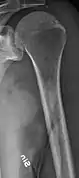

Medical imaging

The diagnostic examination of a person with suspected multiple myeloma typically includes a skeletal survey. This is a series of X-rays of the skull, axial skeleton, and proximal long bones. Myeloma activity sometimes appears as "lytic lesions" (with local disappearance of normal bone due to resorption). And on the skull X-ray as "punched-out lesions" (pepper-pot skull). Lesions may also be sclerotic, which is seen as radiodense.[47] Overall, the radiodensity of myeloma is between −30 and 120 Hounsfield units (HU).[48] Magnetic resonance imaging is more sensitive than simple X-rays in the detection of lytic lesions, and may supersede a skeletal survey, especially when vertebral disease is suspected. Occasionally, a CT scan is performed to measure the size of soft-tissue plasmacytomas. Bone scans are typically not of any additional value in the workup of people with myeloma (no new bone formation; lytic lesions not well visualized on bone scan).